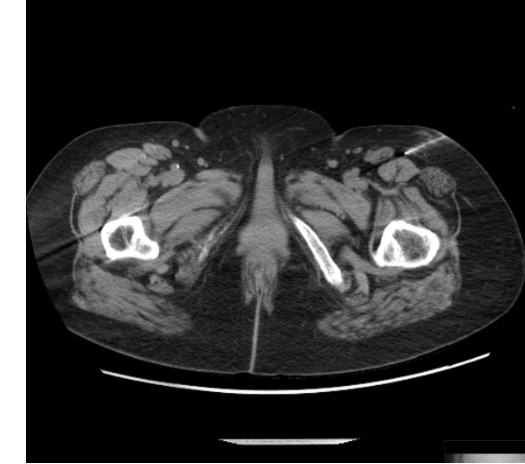

Obturator Nerve

- Arises from L2–L4; exits pelvis through obturator foramen

- Divides into anterior branch (hip adductors, medial thigh sensation) and posterior branch

- Target: CT-guided; obturator foramen or medial to femoral vessels

- Approach: CT supine; coronal plane most useful; 22G needle

- Motor risk: adductor weakness — counsel about driving

| Nerve | CT Target | Best CT Plane | Key Anatomy |

|---|---|---|---|

| Obturator | Obturator foramen; medial to femoral vessels | Coronal (most useful) | Anterior / posterior division at foramen |